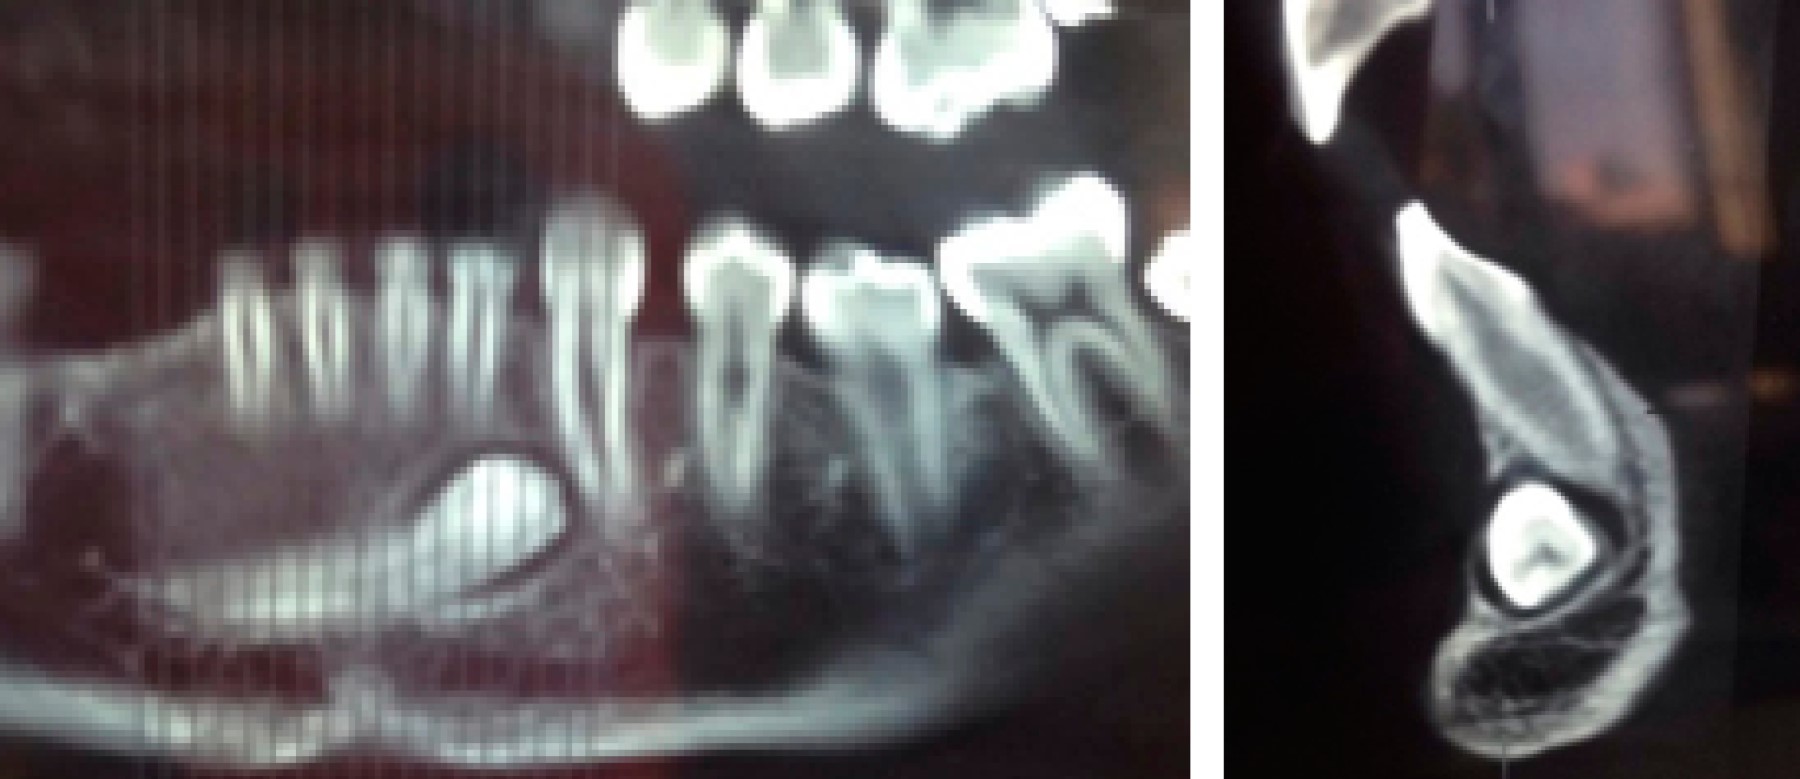

La posición radicular está al centro del reborde y la zona vestibular de la corona en relación a los OD 3.1 y 3.2. No se observan imágenes sugerentes de reabsorción radicular anómala a nivel de incisivos inferiores (Figura 3). Se observa que el canino ya cruzó más allá de la línea media y se encuentra en una etapa de desarrollo muy avanzada con la formación de la raíz casi completa. Por lo anterior, las posibilidades de realizar un tratamiento de ortodoncia exitoso y posicionar la pieza en una posición correcta son casi inexistentes, por lo que el tratamiento a seguir fue la extracción dentaria, descartando el trasplante por ausencia del espacio interdentario necesario.

Figura 3